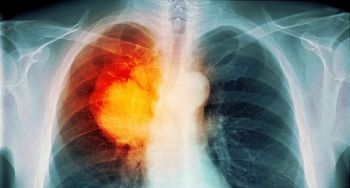

Ung thư phổi là một trong 3 loại ung thư thường gặp nhất và là nguyên nhân gây tử vong hàng đầu do ung thư ở phạm vi toàn cầu. Theo thống ...